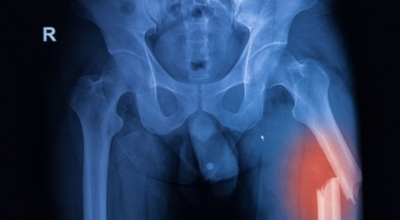

나이가 들면 흔히 생기는 질환 중 하나입니다. 관절을 보호하고 있는 연골의 손상이나 퇴행성 변화로 인해 관절을 이루는 뼈와 인대 등에 손상이 생겨 염증과 통증이 발생하는 질환입니다. 고관절 쪽 연골이 닳게 되면서 망가지게 되고 또 쉽게 없어지지 않는 통증에 시달릴 수 있습니다.

고관절 통증 치료에는 크게 약물 치료와 물리 치료가 있습니다. 고관절염의 진행을 늦추거나 증상을 완화하기 위한 목적으로 항염증제 및 진통제를 투여합니다. 고관절 통증을 조기에 치료하면 약물치료 외에 물리치료로 약 50% 정도 큰 효과를 볼 수 있습니다. 게다가, 보통 고관절 증상 관리에 도움이 되는 요가, 수영, 스트레칭은 고관절 예방과 치료에 도움이 됩니다.